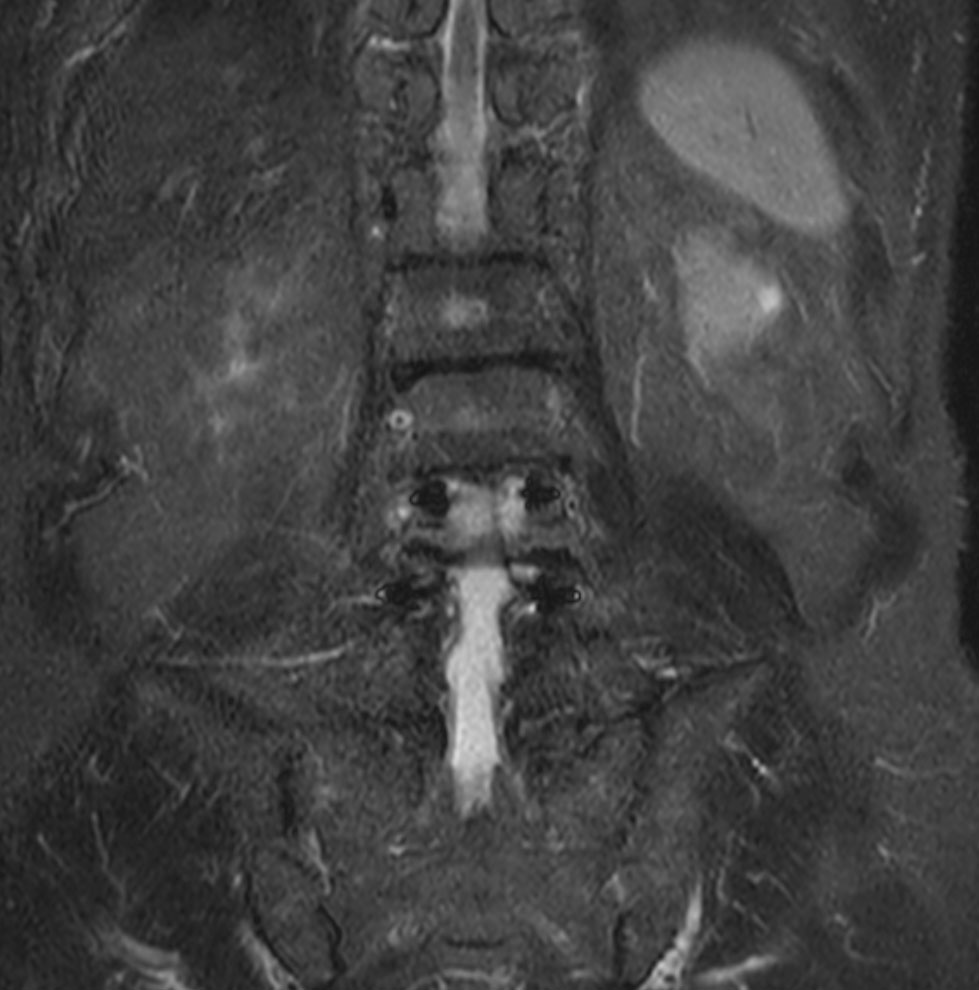

Coronal 3D T2w TSE (VISTA)

Coronal STIR TSE